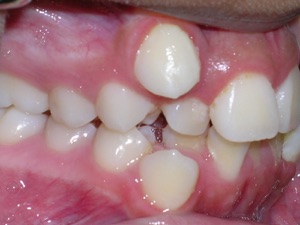

Here’s an example from a young boy who had very significant crowding. One can see that the canines on top and bottom are blocked out. There was also an overbite. The combination made the case challenging. Watch.